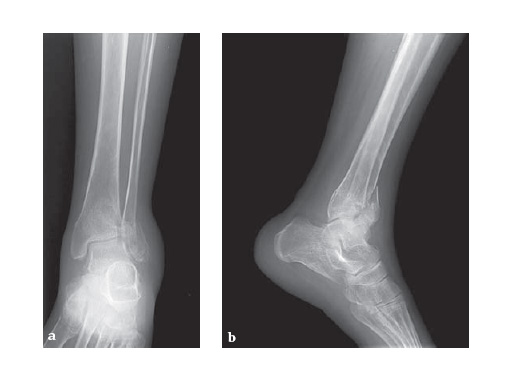

Clinical case:

28-year-old woman had a high energy motor vehicle collision and sustained an isolated distal left tibial fracture.